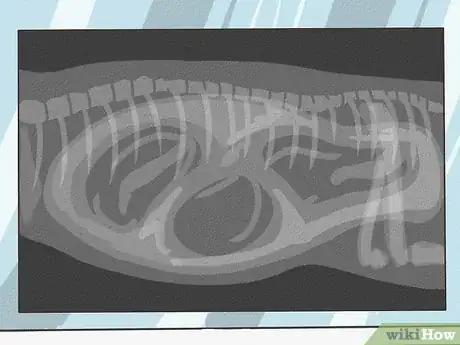

QuestionWhy do they X-ray pregnant dogs?

Licensed Veterinarian Some breeders like to get X-rays so they can check for and count the number of puppies. Not all breeders do this, though.

Some breeders like to get X-rays so they can check for and count the number of puppies. Not all breeders do this, though. -